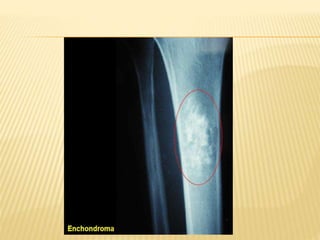

ENCHONDROMA

 Benign hyaline cartilage tumor occur in medulla of

bone and cause destruction of cancellous bone

 Replaces normal bone with mineralized/un. Hyaline

cartilage

 AGE: Most common between 2nd & 4th decades

 SITES: Short tubular bones of hand (phalanges and

metacarpals), followed by metaphysis femur,

humerus and ribs

 c/o- painless swelling,pain due to patho#

 RADIOGRAPHS: well circumscribed distinct area of

rarefaction, expands the cortex ,

 Calcification in older lesions -

spotty/punctate/stippled-rings & arcs